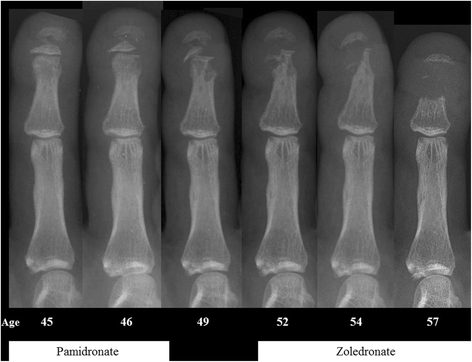

Background: Hajdu-Cheney syndrome (HCS) (#OMIM 102500) is a rare, autosomal dominant condition that presents in early childhood. It is caused by mutations in the terminal exon of NOTCH2, which encodes the transmembrane NOTCH2 receptor. This pathway is involved in the coupled processes of bone formation and resorption. The skeletal features of HCS include acro-osteolysis of the digits and osteoporosis commonly affecting vertebrae and long bones. Fractures are a prominent feature and are associated with significant morbidity. There is no specific treatment, but with both acro-osteolysis and generalized osteoporosis, it is possible that anti-resorptive treatment might be of benefit. However, to date only a few case reports have evaluated the effectiveness of bisphosphonate treatment.

Results: The mean lumbar spine bone mineral density (BMD) z-score before treatment was - 2.9 (SD 1.2). In 14 courses of treatment (82%), there was an increase in BMD with bisphosphonate treatment, but the impact (in terms of change in spinal BMD z-score) appeared to be less with advancing age (p = 0.01). There was no evidence that acro-osteolysis was prevented.